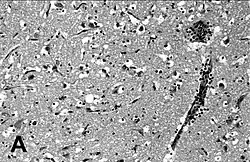

| Encephalitis in the cerebral cortex of a harbor seal with PDV, stained with hematoxylin and eosin | |

Phocine distemper virus (PDV), is a paramyxovirus of the genus Morbillivirus that is pathogenic for pinniped species, particularly seals.[2] Clinical signs include laboured breathing, fever and nervous symptoms.